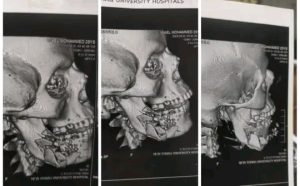

صرح الدكتور حسان النعماني رئيس جامعة سوهاج، أن قسم الطوارئ بالمستشفي الجامعي الجديد استقبل شاباً مصاب بطلق ناري بعظام الرقبة والوجه، وبشكل عاجل تم تشكيل فريق طبي متخصص من وحدة جراحات الوجه والفكين، وبالتعاون مع قسم التخدير، تم التعامل مع الحالة وعمل الاسعافات الأولية اللازمة لوقف النزيف وتركيب المحاليل، لاستقرار الحالة الصحية العامة وتجهيزه لدخول العمليات بشكل عاجل.

ومن جانبه قال الدكتور مجدي القاضي عميد كلية الطب البشري، إن المريض حضر الي المستشفي الجامعي في حالة سيئة نتيجة إدعاء طلق ناري بعظام الرقبة والوجه، حيث نجح الفريق الطبي في إنقاذ حياة المريض بعد إجراء عملية جراحية استغرقت عدة ساعات، وتحتاج إلى مهارة ودقة عالية في إجرائها.

وقال الدكتور سمير عبدالمجيد مدير مستشفي الطوارئ إنه تم نقل المريض على وجه السرعة لعمليات جراحة الوجه والفكين، وتوفير كافة المستلزمات والمعدات لإجراء تلك الجراحة، والتواصل مع الأقسام المختصة بالمستشفى الجامعي لإنقاذ حياة الشاب.

وقال الدكتور اسلام عامر أنه استكاملاً لما تقوم به وحدة جراحات الوجه والفكين من عملها المستمر في استقبال حالات الاصابات المختلفة وتقديم اعلي رعاية صحية عاجلة، وبتكليف من الدكتور كمال الشرقاوي رئيس قسم الجراحة العام، تم التعامل مع الحالة بتثبيت الكسور بعملية نوعية، والتعامل مع حالة المريض بعناية ودقة شديدة، من خلال فريق طبي مكون من الدكتور محمود فهمي معيد بجراحة الوجه والفكين، وبالتعاون مع قسم التخدير والهيئة التمريضية المعاونة.